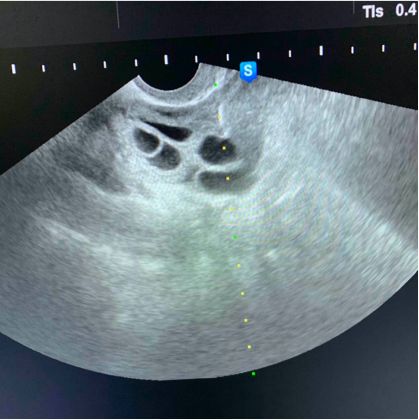

其实现在的取卵手术比较简单,就是在阴道超声的监护下,用一根细细长长的取卵针扎入卵泡中,通过负压吸引将卵子取出体外的技术。

像这种情况,穿刺针进去就是卵泡,还没来得及疼呢手术就结束了!